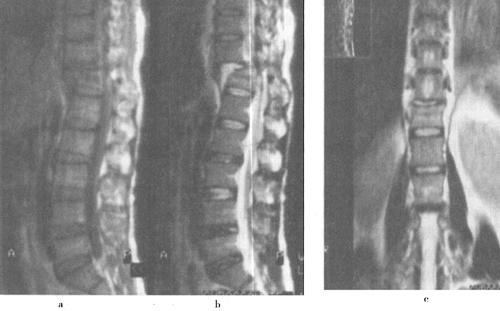

(2)出血:包括脊髓内出血和硬膜外血肿(图7-14至图7-16)、硬膜下出血和蛛网膜下腔出血等。脊髓内出血是不可逆损伤,其信号改变随时间变化较大。急性期(24h内)髓内出血灶在T1WI呈中等信号或不均匀信号,在T2WI呈中央低信号出血灶,外围水肿为高信号。亚急性期(3~5d)血肿在T1WI信号逐渐升高,在T2WI信号仍较低,慢性期血肿在T1WI和T2WI均为高信号。脊髓硬膜外血肿、硬膜下出血和蛛网膜下腔出血,在MRI上表现为椎管内脊髓外的软组织增厚影,在T1WI呈不均匀低信号,在T2WI为高信号。硬膜外出血脊髓受压移位明显。

图7-14 腰椎后柱骨折伴硬膜外出血,马尾受压。T1W(a)和T2W(b)矢状成像,椎管后方硬膜外可见T1W和T2W均为高信号的血肿

图7-15 颈髓挫裂伤:T1W(a)T2W(b)矢状面,脊髓增粒为髓水肿所致,T1W和T2W信号增高。横断面(c)脊髓内可见斑片状出血灶,硬膜外血肿T2W亦呈高信号,脊髓压迫向右后移位。颈后方软组织出血水肿,在T2W亦为高信号

图7-16 L1压缩骨折,脊髓挫裂伤:T1W(a)和T2W(b)矢状面,L1椎体呈楔状变形,椎体骨折,但无移位。后方硬膜外及脊髓内可见高信号血肿,在横断位T1W(c)、T2W(d)成像,如箭头所示脊髓圆锥内椭圆型高信号影,为出血所致。椎体骨髓水肿及出血。

(3)脊髓挫伤:脊髓挫伤是脊髓水肿伴局灶性出血,在T1WI小的出血灶可呈高信号,邻近水肿为等低信号,T2WI呈混杂高信号(图7-16)。

(4)脊髓受压:脊髓受压变扁变形,局部脊髓信号强度可正常或T2WI信号轻度增高(图7-17)。通常是由于脊柱骨折和脱位,使椎管变形、狭窄所造成,多见于椎体的爆裂性骨折、过屈过伸性损伤、旋转性创伤和单纯的压缩性骨折等,这些创伤往往伴有严重的肌腱和韧带损伤。

图7-17 T12压缩性骨折并脊髓横断性损伤:T1W(a)和T2W(b)矢状面扫描,可见T1压缩变扁,T11以上向前移位,脊髓呈横断性改变。椎间盘及脊柱前纵韧带下血肿。冠状面脊柱两侧亦见高信号出血

(5)脊髓横断:脊髓横断表现为脊髓和硬膜囊连续性中断,在矢状面显示清楚。完全性横断可伴有脊髓的回缩,两断端出现较宽的间隙。MRI检查T2WI较T1WI敏感,可清楚显示横断的脊髓,尤其是在T2WI,脑脊液呈高信号,而脊髓呈中等信号,两断端间充满高信号的脑脊液(图7-18)。不完全性脊髓横断,在T2W呈高信号,脊髓连续性尚存。

图7-18 T11椎体骨折脱位伴脊髓横断性损伤:T1W(a)和T2Wb矢状面示,T10以上明显向前脱位,椎管和脊髓在T11水平中断和成角,脊椎前、中、后柱骨折脱位,并有脊柱周围血肿